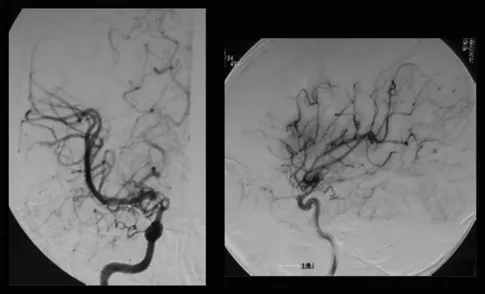

MRI没有发现脑卒中病变,但基底节有多个血流空洞。MRA显示右颅内颈内动脉末端狭窄,左颈内动脉造影显示颈内动脉无狭窄,右大脑前动脉由左大脑前动脉经前连合动脉供血。右颈内动脉造影显示颈内动脉末端狭窄,大脑前动脉缺失,大脑中动脉较左动脉扩张,烟雾血管在颈内动脉顶部形成(图1)。氙-CT灌注成像技术Xe-CT静息时及负荷时对比,显示右侧大脑中动脉区脑血管反应为14.8%,与左侧相比,右侧大脑中动脉区域的血供摄取没有明显减少(图2)。

图1:术前右颈血管造影显示,在颈内动脉末端顶部,血管烟雾弥漫性发育,大脑中动脉扩张